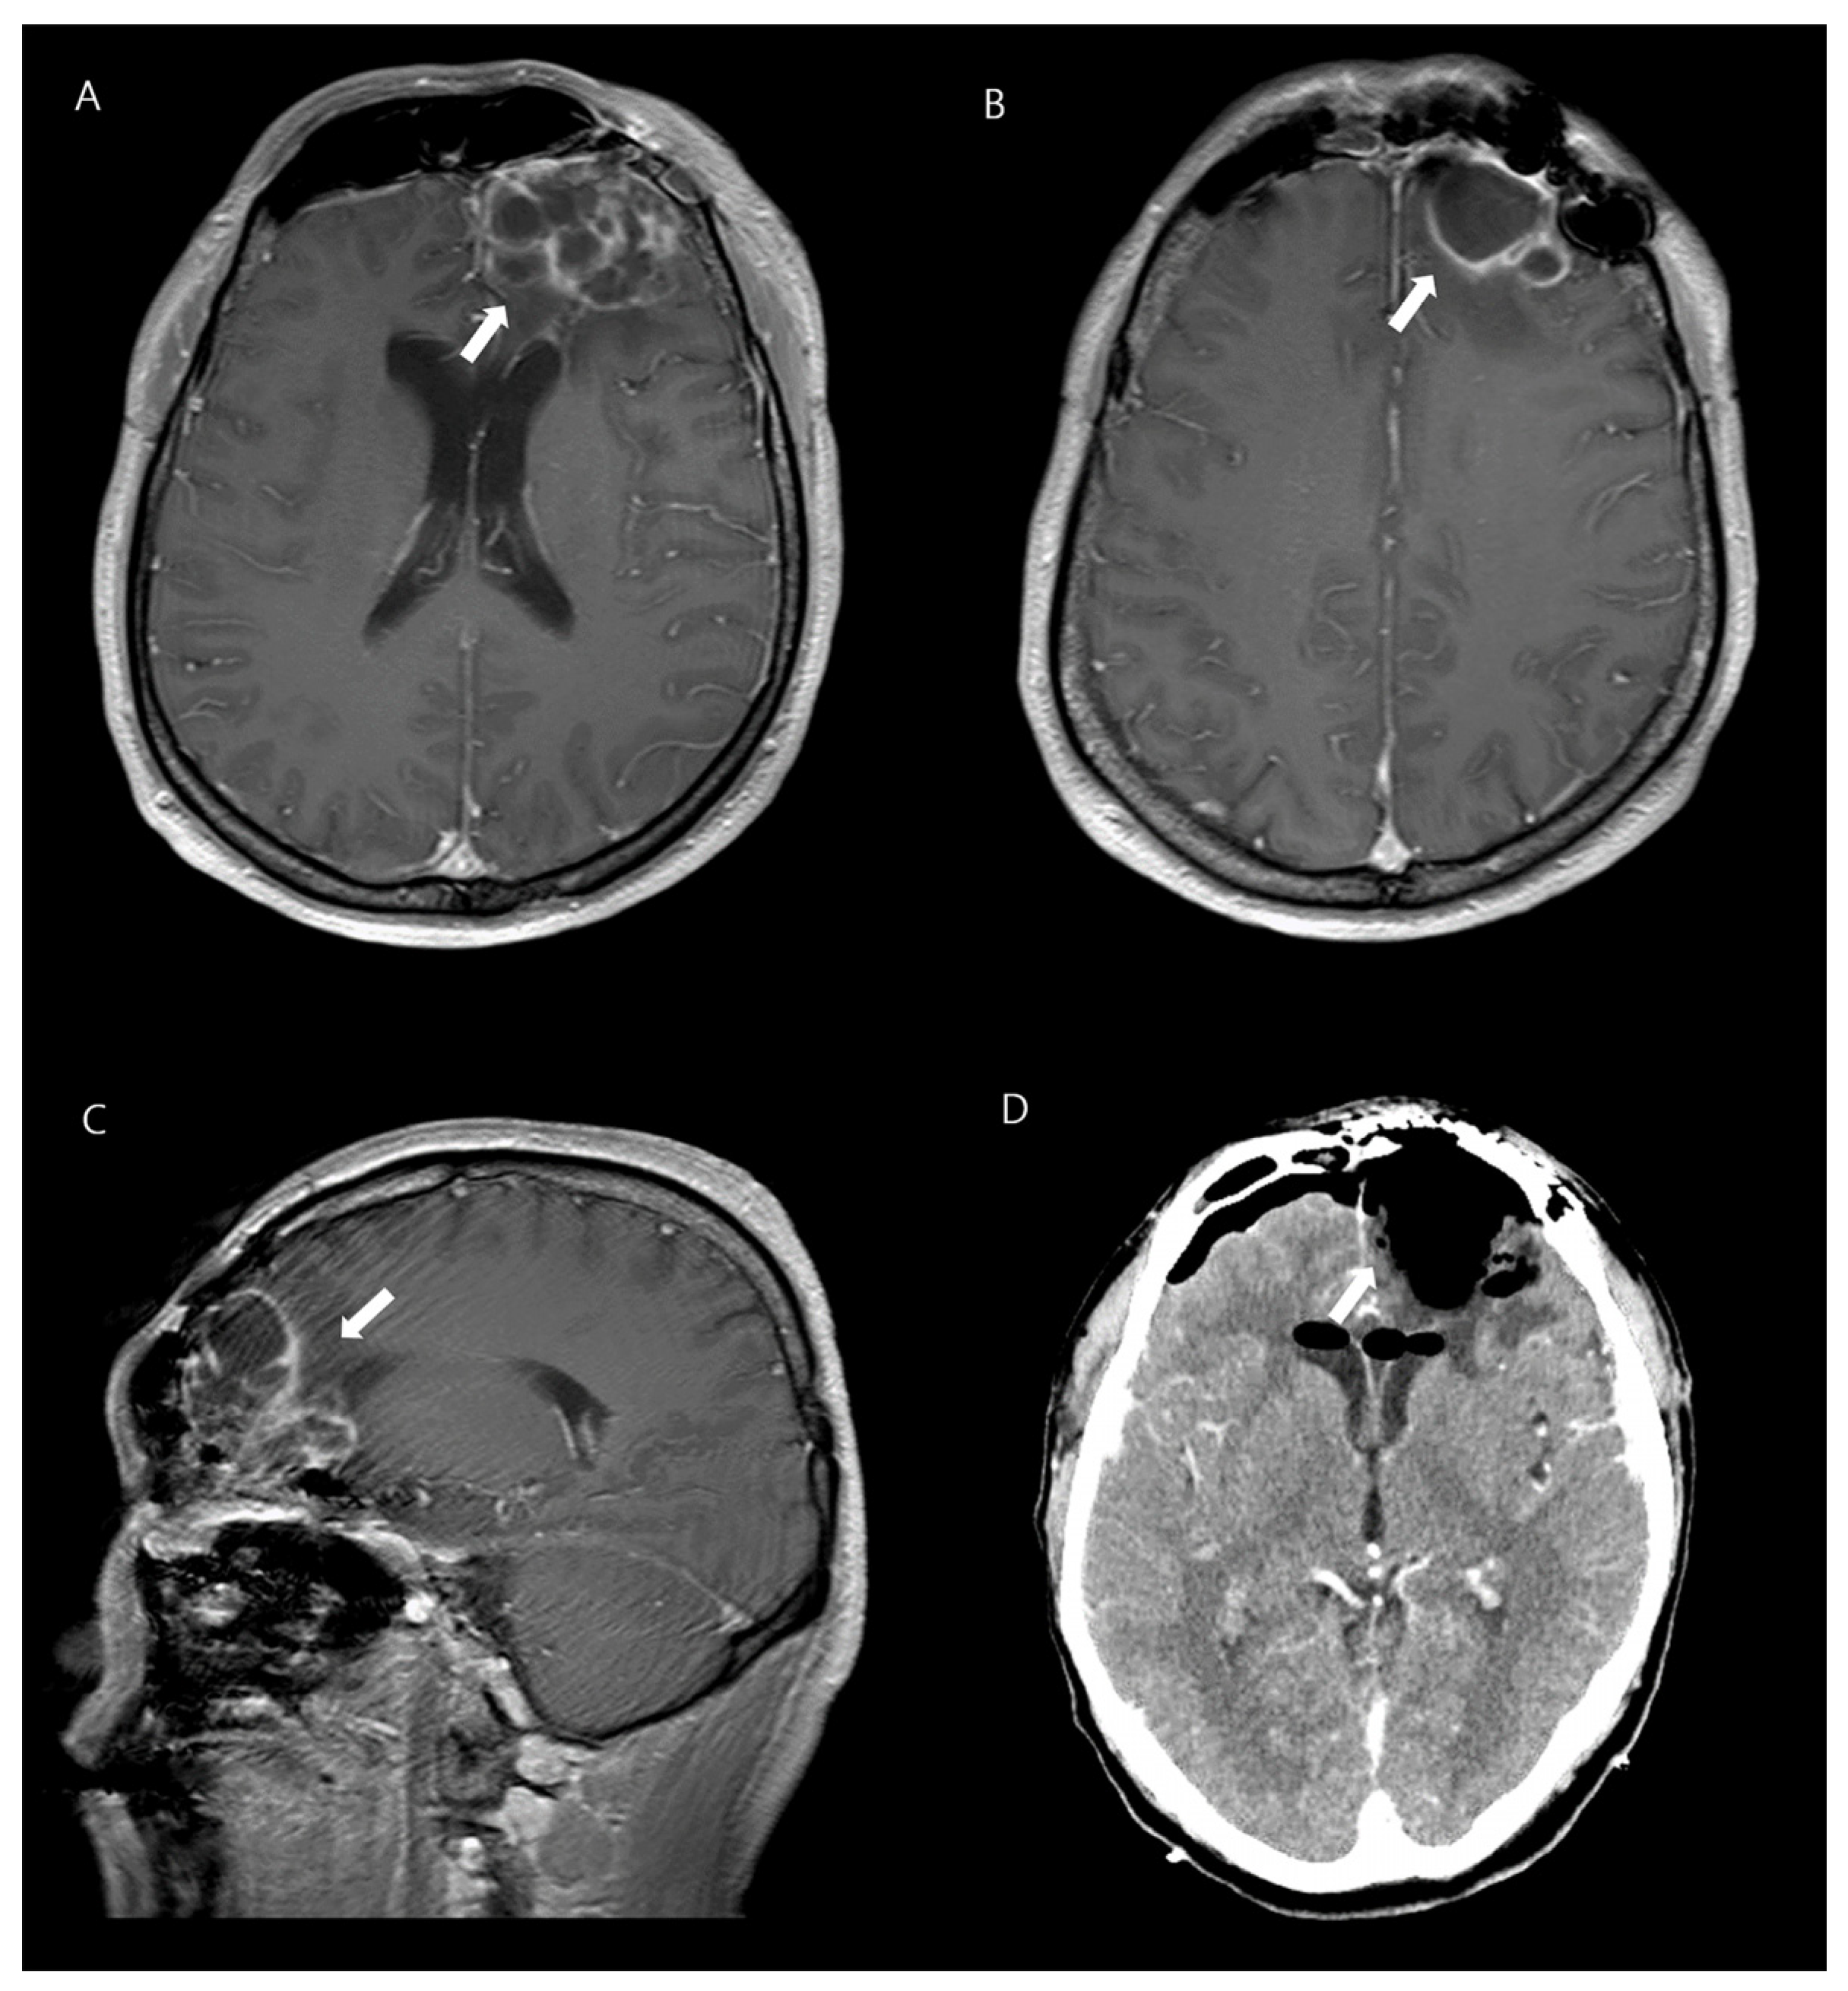

Further investigations, including a lumbar puncture, were performed. The patient’s biochemistry and hematology panel showed normal liver and renal function, as well as an absence of leukocytosis with a normal differential cell count, except for elevated levels of high-sensitivity C-reactive protein (109.4 mg/L) and procalcitonin (1.98 ng/mL). Urinalysis was normal. Analysis of cerebrospinal fluid (CSF) obtained through lumbar puncture showed a cloudy appearance; elevated white blood cell count of 2460/mm3, with a predominance of neutrophils (81%); and abnormal protein and glucose levels (510.7 mg/dL and 5 mg/dL, respectively). The patient’s intracranial pressure was found to be elevated at 190 mmH2O. Gram staining of the CSF did not show any microorganisms and cultures were negative. However, blood cultures showed K. pneumoniae growth. Nasopharyngeal swab culture was taken to identify K. pneumoniae colonization, and it tested positive. A chest X-ray; computed tomography (CT) scan of the chest, abdomen, and pelvis; electrocardiogram; and transthoracic echocardiogram were performed, all of which revealed no abnormalities. However, magnetic resonance imaging (MRI) of his brain revealed a lobulated lesion with rim enhancement, suggestive of abscess, in the left frontal area and craniotomy site, and showed evidence of ventriculitis and empyema in both lateral ventricles (Figure 1).

Figure 1. A 42-year-old man with K. pneumoniae brain abscesses. Axial contrast-enhanced T1-weighted images (A,B) and sagittal image reveal thin-walled rim-enhancing abscesses in the left frontal lobe (C). Enhanced brain CT shows disappeared lesions after the neurosurgery (D).